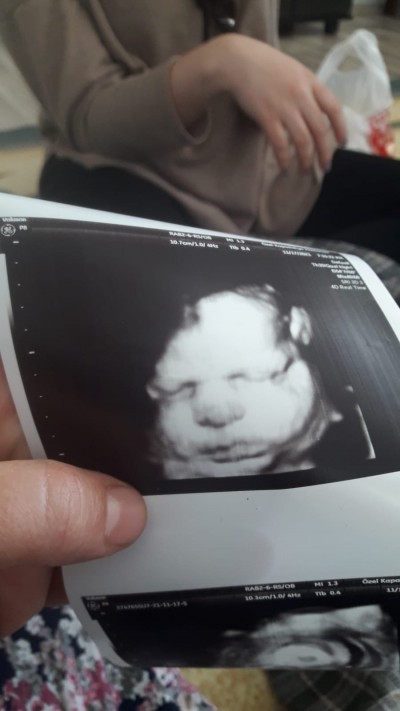

9 aylik hamilelik ultrason resmi cinsiyet tahmini yapar mısınız

Gebelik haftası 39

Attim resim

Attim simdi resim

Erkek bence :) ama bebektir yani erkek de olsa kiz da olsa aynı gorunur yüz şekli bebiş yani bebek yüzlü adı üstündee bebeeeeekkk :)))

Çene şeklinden ayırt ediliyormuş

Kiz demis doktor

Kız çünkü yüzü kibar.. Erkek bebeklerinki biraz daha kaba.. Çünkü bizimki kaba

Valla cinsiyeti anlamadım ama kesin olan bişey var ki coookk tatlı bir bebiş geliyor Allah sağlıkla kucağınıza almayı nasip etsin

Kiz bence kiza benzettdim

Ya ne güzel yüzü çıkmış benim hiç yok böyle yüzünü hiç göremedik

Kacinci ayinda yüz şekli boyle gorunuyor ultrasonda

erkek bu canım

Bebegin yuzunden cinsiyet belli olmaz ki

Çene seklini kas ettim